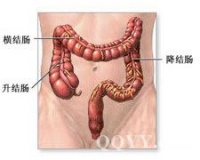

肠梗阻是肠腔的物理性或机能性阻塞、发病部位主要为小肠。小肠肠腔发生机械阻塞或小肠正常生理位置发生不可逆变化(肠套叠、嵌闭和扭转等)。小肠梗阻不仅使肠腔机械性不通,而且伴随局部血液循环严重障碍,致使动物剧烈腹痛。呕吐或休克等变化,本病发生急剧。病程发展迅速,预后慎重,如治疗不及时死亡率高。